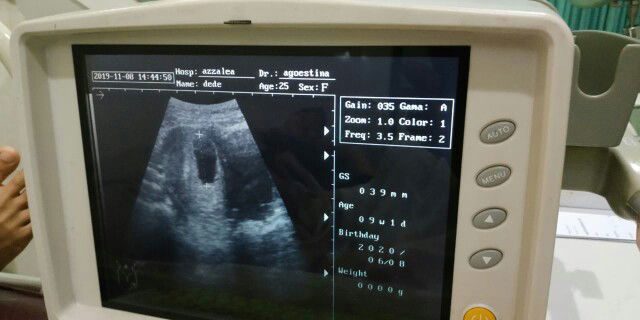

Baru 9 minggu

Ibu hamil